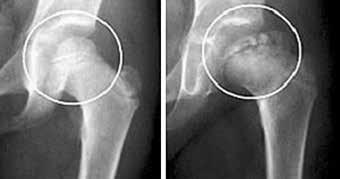

Development of an Internal Offloading/Distraction Device

Perthes disease is an idiopathic childhood condition that occurs when the blood supply to the femoral head ( Figure 1 ) is disrupted, leading to osteonecrosis, or bone cell death. It is one of the most common hip disorders in children, and the risk of a child developing this condition is about 1 out of every 1200 children over his or her lifetime. As the condition progresses, the femoral head gradually begins to break apart as shown in Figure 2. If left untreated, the femoral head can deform and not correctly behave as a ball-and-socket joint in the acetabulum, leading to an early onset of arthritis. This can develop into more serious conditions, such as a total hip replacement for the patient in his or her teens.

or separates, the femoral head from the acetabulum, which helps restore blood flow to the femoral head, the main objective of the device. It remains attached to the patient until the femoral head returns to a ball-shape, which is usually after 6-12 months. However, there are three primary complications with this device. First, the body is exposed to the external environment, which could potentially let the body be susceptible to infections. Another problem that the external fixator presents is that, since the device is quite large, there is a large bending moment placed upon the device. This can lead to pivoting of the screws, causing microfractures in the device. In turn, this can potentially lead to larger, more serious bone fractures. Finally, there’s only one axis of rotation for the leg – flexion/extension. This axis of motion is shown in Figure 4. This is a particularly challenging risk, as children tend to run, jump, bounce, and perform a variety of other motions with their legs.

Current Treatment

Current treatment of Perthes disease involves an external fixator, which stabilizes the bone and tissue from outside of the body as seen in Figure 3. This external fixator distracts,

Figure 1. Anatomy of human hip and femur: The femur and acetabulum form a ball-and-socket joint which allows the hip to move freely about the femoral head. Figure 2. X-ray of Perthes disease: A normal femoral head is displayed on the left and a femoral head affected by Perthes disease is displayed on the right. The femoral head on the right does not receive nutrients from the blood, resulting in bone cell death. Figure 3. Current solution - external fixator: On the left is the device currently used by Scottish Rite Hospital for Children, and the diagram on the right is a basic overview of how the device is fixed to the body for stabilization purposes